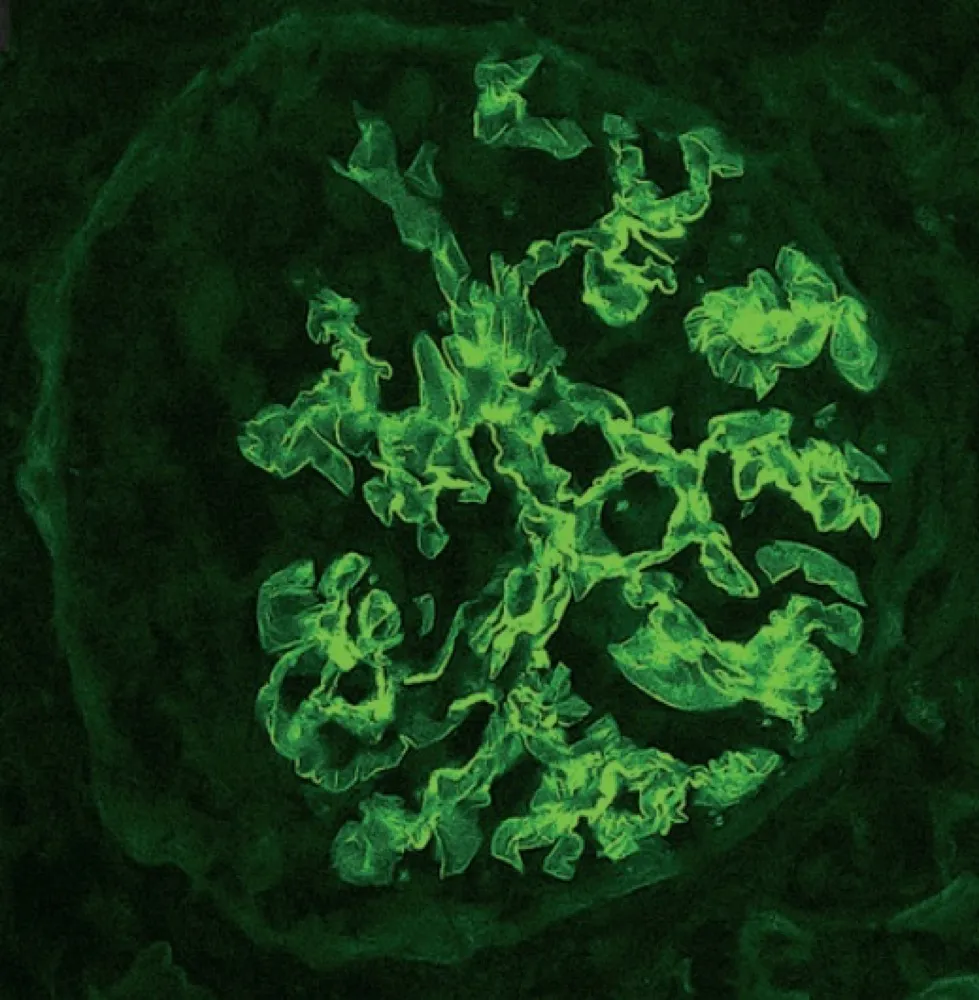

Idoso com GNRP, qual seria sua principal hipótese diagnóstica?

Idoso com GNRP, qual seria sua principal hipótese diagnóstica?Caso típico de GNRP em paciente idosos. Vendo a imagem, qual seria sua primeira hipótese diagnóstica?